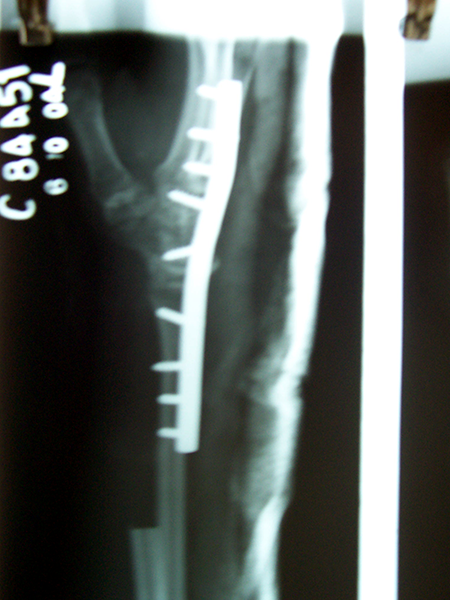

Case:5 Ewing sarcoma with implant failure

Orthopedic Oncology Doctor In Ahmedabad

Breakage of Nail

Sports Injuries Doctor

Refixation with Angle Bladed Plate and Sever Graft

Spine Best doctor

Ewing's Post Nailing and Bone Grafting

Best Trauma Surgeon in Ahmedbad

3 Months Post -Op

Joint Replacement

6 Months Post-Op